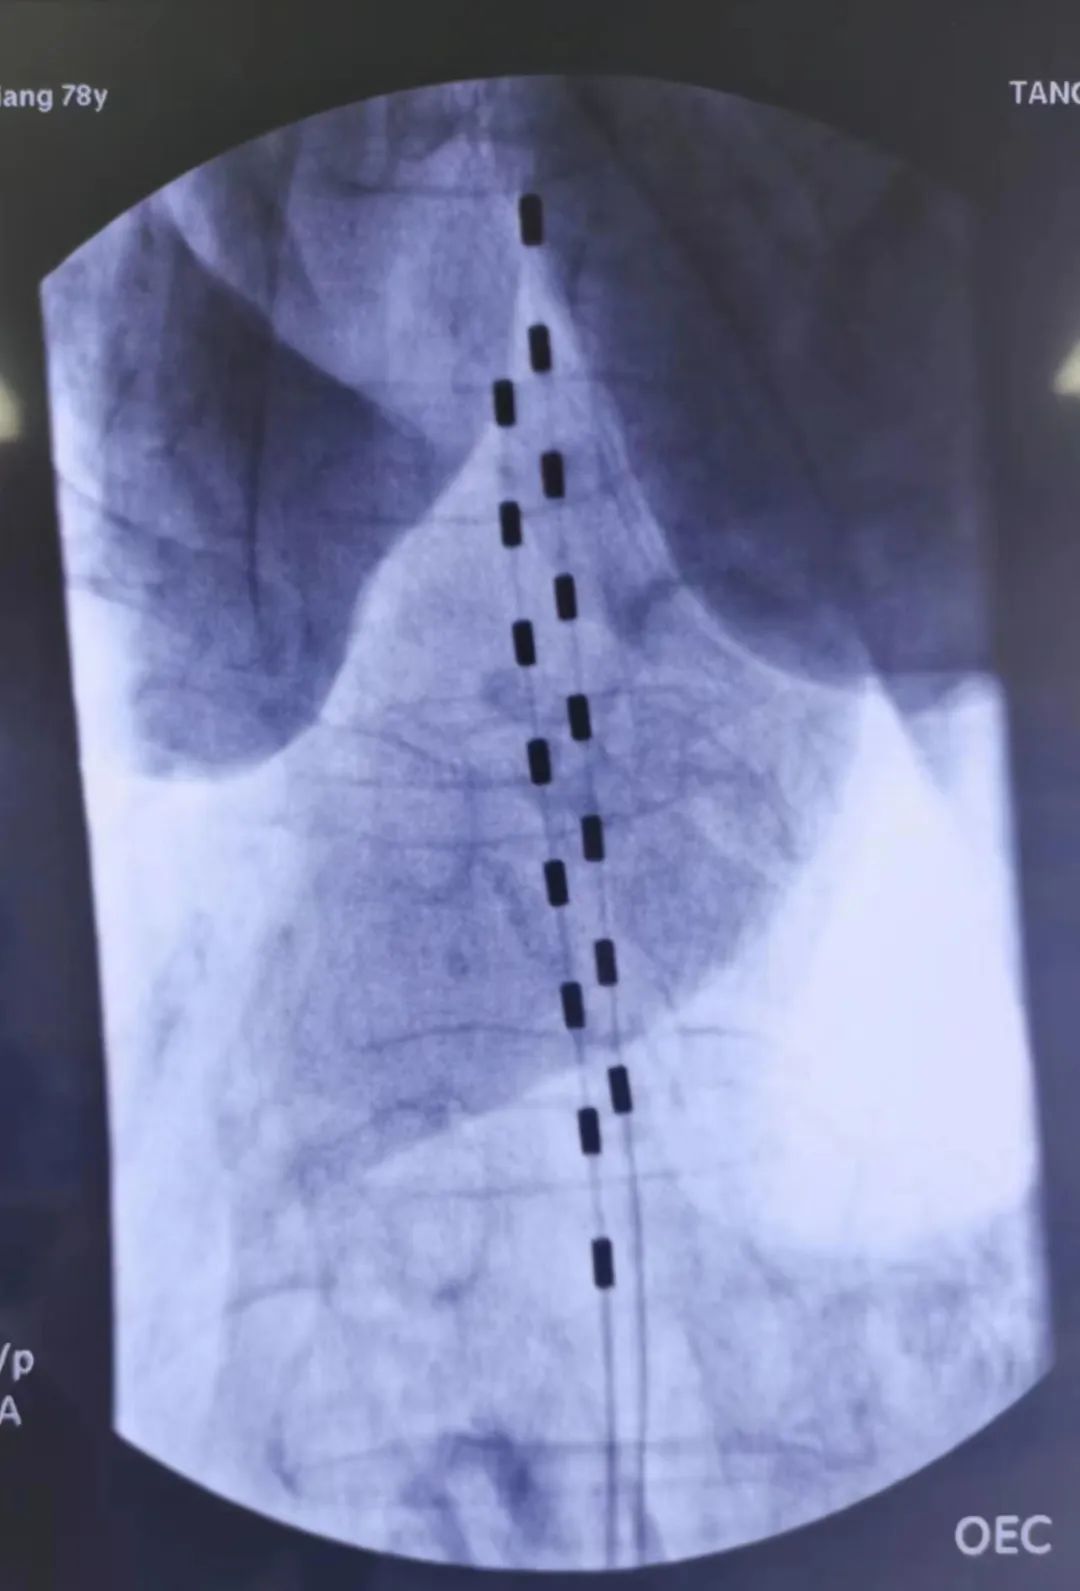

植入后电极及神经刺激器位置

术后,又联合内分泌及烧伤整形科进行血糖控制及创面管理,经过一个月的努力,张阿姨下肢皮肤温度较前回升,左足创面呈逐渐愈合趋势。